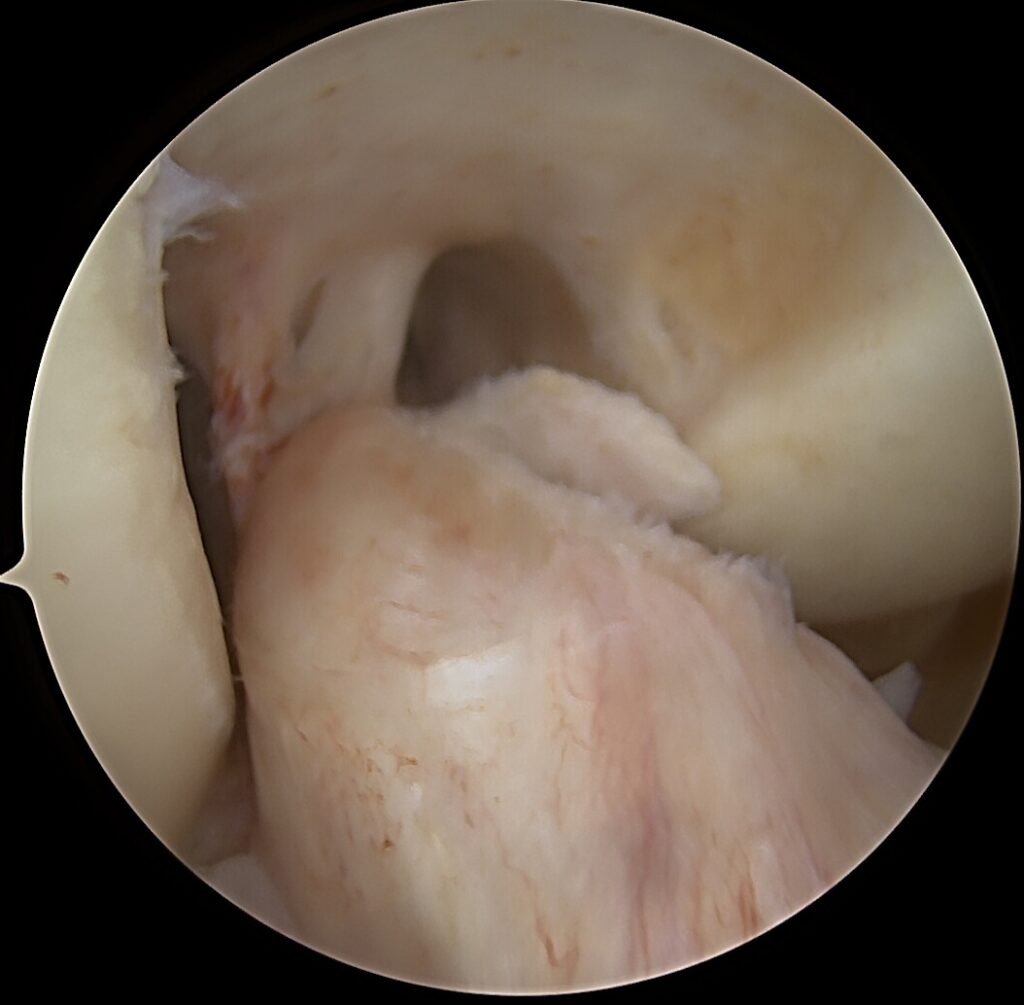

Blauzdos kaulų išnirimas – viena sunkiausių ortopedinių traumų, dažniausiai lydima kelių kelio sąnario raiščių plyšimų, kraujagyslių ir nervų pažeidimų rizikos. Tokios traumos dažnos po aukštos energijos sužalojimų: eismo įvykių, kritimų iš aukščio ar kontaktinio sporto. Sunki kelio sąnario trauma: blauzdos kaulų išnirimo gydymas atliekant daugiaraištę kelio rekonstrukciją – yra iššūkis ne tik ortopedo komandai, bet ir pačiam pacientui.

Sunki kelio sąnario trauma: blauzdos kaulų išnirimo gydymas atliekant daugiaraištę kelio rekonstrukciją nėra lengva chirurginė procedūra, reikia labai tiksliai žinoti kelio anatomiją.

✔️ Priekinio kryžminio raiščio (ACL) ir užpakalinio kryžminio raiščio (PCL) rekonstrukcija – atstato priekinį ir užpakalinį stabilumą